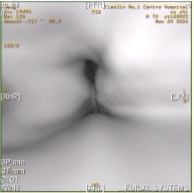

患者男,60岁,声音嘶哑半年,CT表现如下图。

诊断正确的是

A.声门区喉癌

B.声门上喉癌

C.喉正常表现

D.喉结核

E.喉乳头状瘤